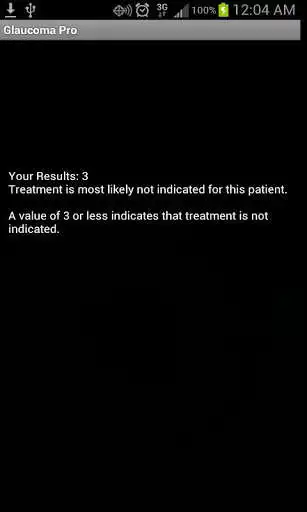

This app is based upon the journal article titled "For which glaucoma suspects is it appropriate to initiate

treatment?", published in the journal Ophthalmology. It allows the user to calculate, based upon 7 clinical criteria, whether or not treatment is indicated for a patient.